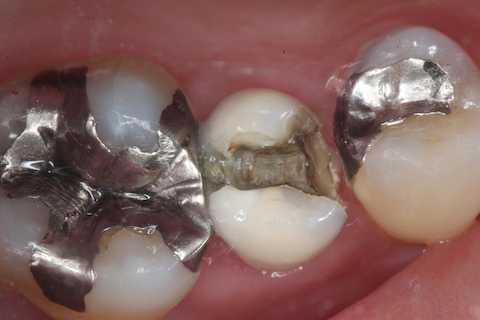

今日の充填治療56(メタルインレー脱離) 2025.01.04